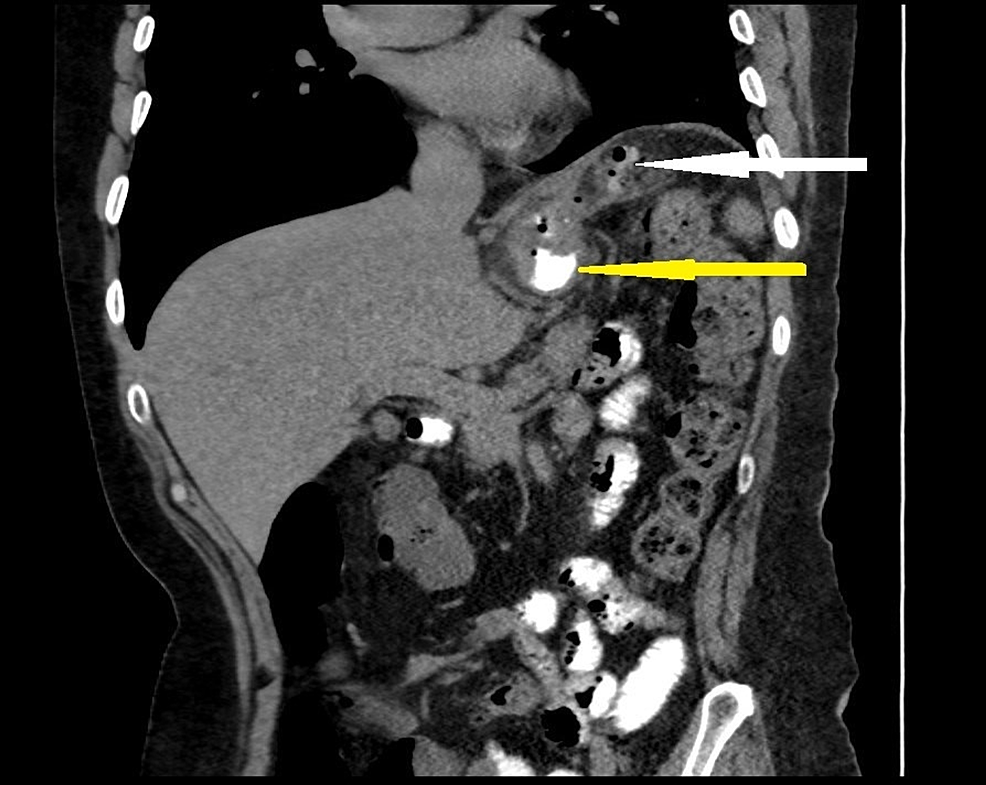

From clinicalimagingscience.org

Computed Tomographybased Diagnosis of Postlaparoscopic Sleeve Post Sleeve Gastrectomy Leak In our review, we noticed that the most important clinical sign or symptom in. Leaks after sleeve gastrectomy remain a deadly complication significantly affecting outcomes and medical costs. • our update for endoscopic treatment of leak following laparoscopic sleeve gastrectomy (lsg) contributes with new data. A missed or delayed diagnosis can. This study aims to share outcomes of our management. Post Sleeve Gastrectomy Leak.

Computed Tomographybased Diagnosis of Postlaparoscopic Sleeve Post Sleeve Gastrectomy Leak • our update for endoscopic treatment of leak following laparoscopic sleeve gastrectomy (lsg) contributes with new data. Sleeve gastrectomy (sg) is the most commonly performed bariatric procedure in the us [1].one of the most common. The presentation of leak after laparoscopic sleeve gastrectomy (lsg) is variable. This study aims to share outcomes of our management algorithm of post lsg leak,. Post Sleeve Gastrectomy Leak.

Computed Tomographybased Diagnosis of Postlaparoscopic Sleeve Post Sleeve Gastrectomy Leak • our update for endoscopic treatment of leak following laparoscopic sleeve gastrectomy (lsg) contributes with new data. The aim of this review was to highlight the causes and thus the prevention modalities and find a standardized algorithm to. Leaks after sleeve gastrectomy remain a deadly complication significantly affecting outcomes and medical costs. The presentation of leak after laparoscopic sleeve gastrectomy. Post Sleeve Gastrectomy Leak.